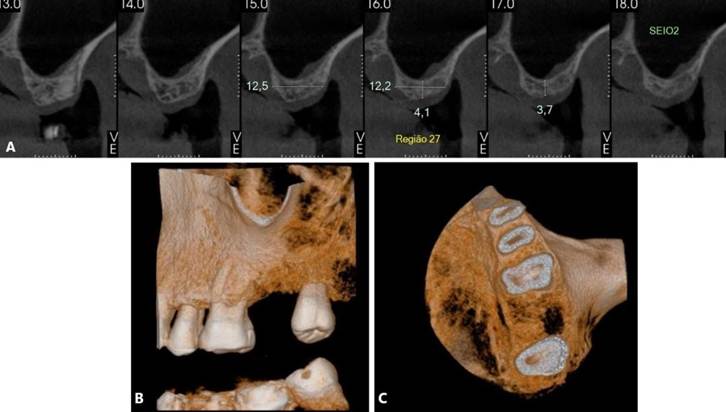

Paciente S. M. T, gênero masculino, 62 anos de idade, compareceu ao consultório particular queixando-se de sintomatologia dolorosa na região do 27. O paciente relatou presenta de insuficiência renal crônica, em tratamento através da hemodiálise. Ao exame clínico e radiográfico, foi proposto a exodontia dos elementos dentários 17 e 27, devido a perda óssea periodontal significativa, inviabilizando a sua manutenção. No mesmo tempo cirúrgico da exodontia, foi realizado a preservação alveolar com enxerto (Bio-Oss, Geistlinch, Wolhusen – Suíça) e membrana (Bio-Gide, Geistlinch, Wolhusen – Suíça). As figuras 15 (A – C) e 16 (A – C) ilustram a TCFC após a extração. Posteriormente, foram instalados implantes curtos ARCSYS (FGM, Joinvile – SC, Brasil) 3,8 mm x 7,0 mm na região do 17, e 4,3 mm x 5,0 mmARCSYS (FGM, Joinvile – SC, Brasil) no 27. O acompanhamento clínico e radiográfico realizado durante 04 anos, com resultados satisfatórios.

Figura 15. A – C) – Tomografia computadorixada de feixe curto (TCFC) evidenciado região edêntula do 17, após exodontia.

Figura 16. A – C) Figura 15. A – C) – Tomografia computadorixada de feixe curto (TCFC) evidenciado região edêntula do 27, após exodontia.